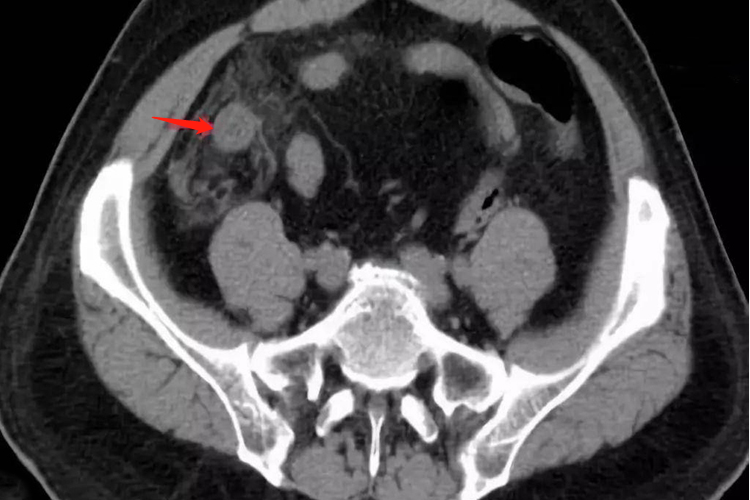

阑尾炎患者超声检查可发现肿大的阑尾或脓肿,而CT敏感性优于超声,治疗方式为手术。

影像学检查一般包括腹部平片、超声和CT,阑尾炎患者进行影像学检查时,腹部平片可见盲肠扩张和液气平面,偶尔可见钙化的肠石和异物影,可帮助诊断。超声检查可发现肿大的阑尾或脓肿。CT的敏感性优于超声,尤其有助于阑尾周围脓肿的诊断。此外,阑尾炎的患者还可能会出现腹痛、厌食、呕吐、乏力等症状。